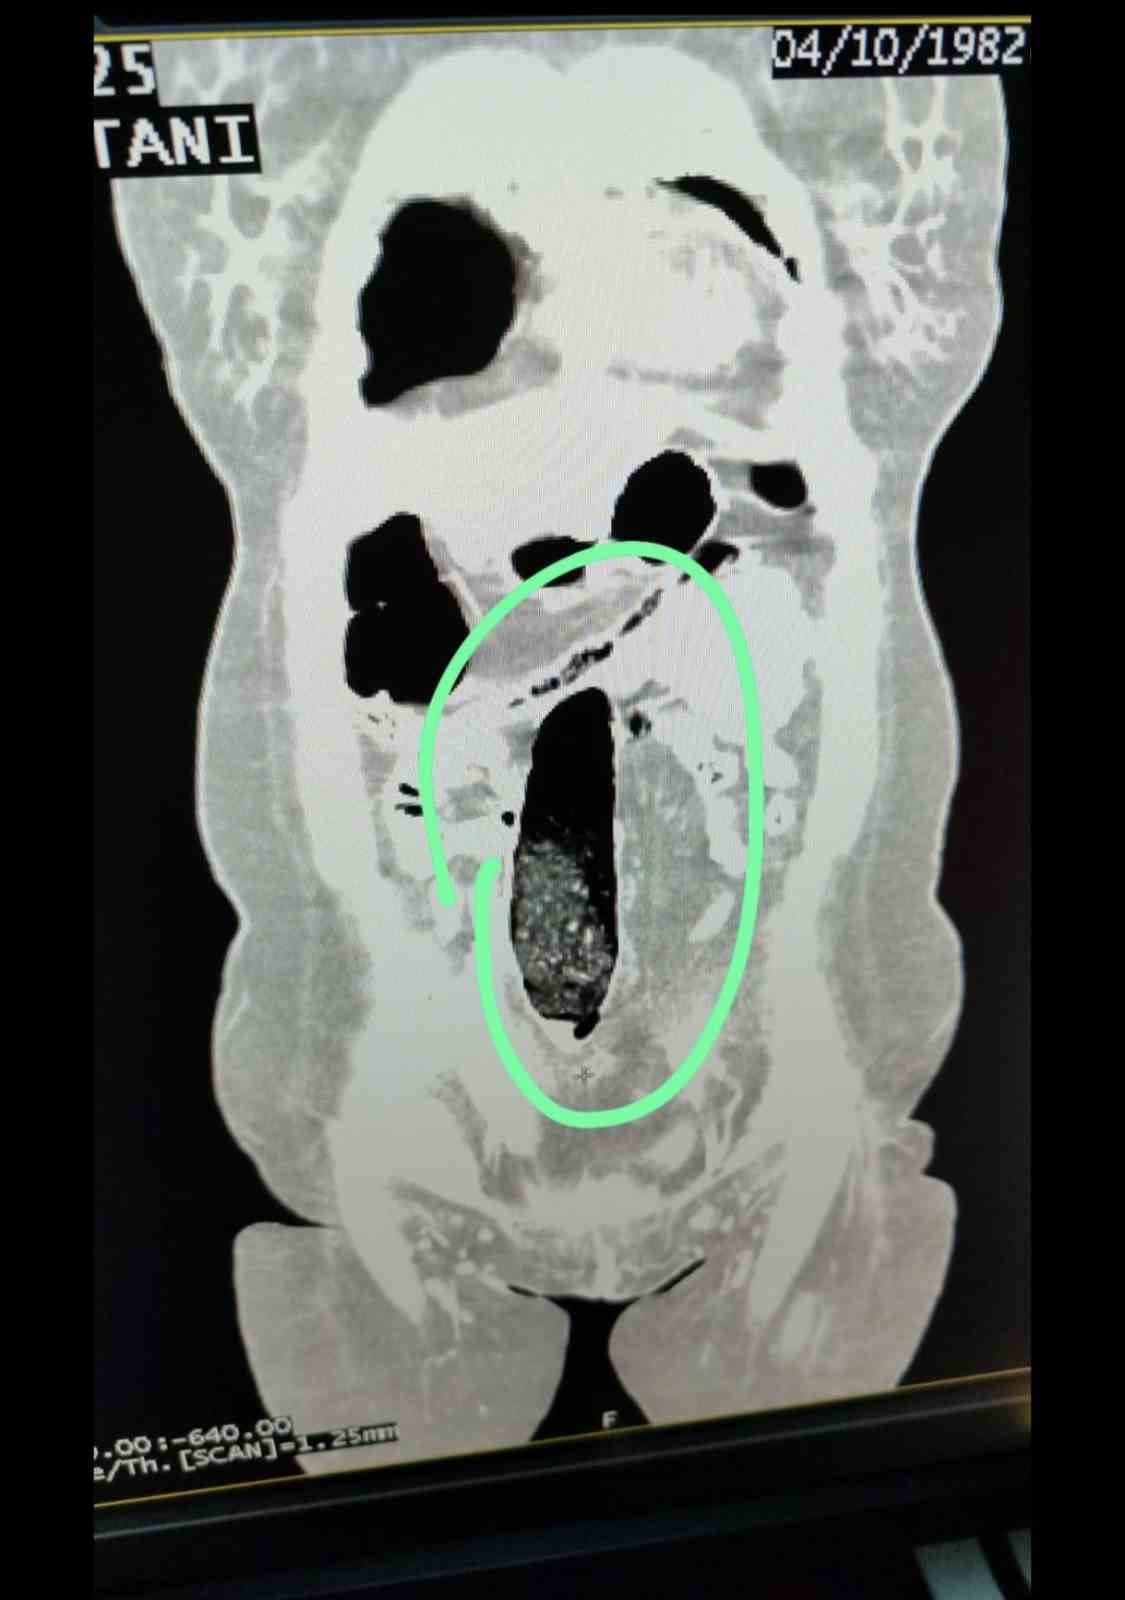

Muş İl Emniyet Müdürlüğü Narkotik Suçlarla Mücadele Şube Müdürlüğü ekiplerince, il genelinde uyuşturucu madde ticareti ve kullanımının önlenmesine yönelik yürütülen teknik ve analiz çalışmaları kapsamında, şehirler arası otobüslerle uyuşturucu sevkiyatı yapılacağı değerlendirildi. Bu değerlendirme üzerine durdurulan şehirler arası yolcu otobüsünde bulunan 2 İran uyruklu şahıs üzerinde yapılan kontrollerde şüpheli durum tespit edildi. Şahısların iç beden muayeneleri sonucunda, vücutlarının doğal boşluklarında ve bağırsaklarında uyuşturucu madde bulunduğu belirlendi.

Tıbbi müdahale sonucu; F.V. isimli kadın şahıstan 3 parça halinde toplam 397,78 gram metamfetamin, S.İ. isimli erkek şahıstan ise 24 adet sentetik hap ile 3 parça halinde toplam 167,68 gram metamfetamin ele geçirildi.